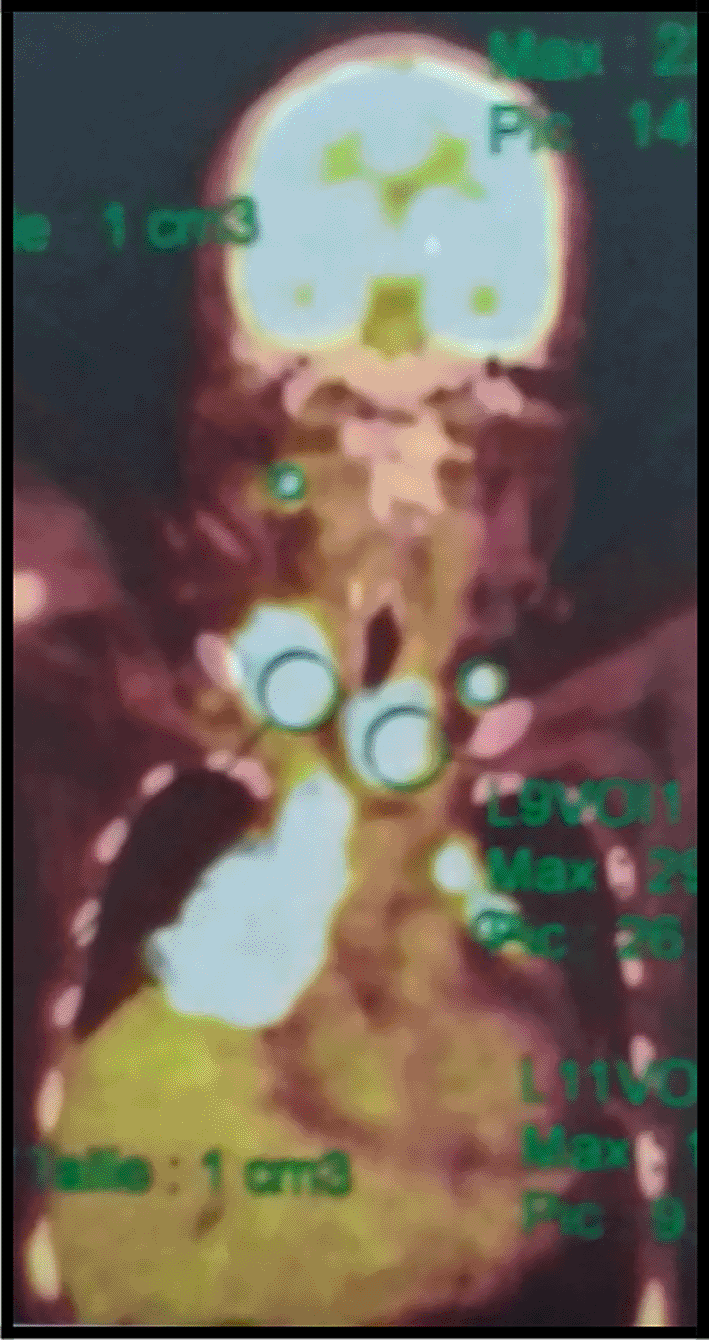

The 18-fluorodeoxyglucose-positron emission tomography (FDG-PET) showed many sites of activity of the disease, with a high metabolic fixation of the FDG in the lymph node stations (1L,3,5,6,7,8,9,10,11R) as well as subphrenic adenopathy. Besides, it revealed an intense endotracheal metabolic fixation (Figures 4, 5). Moreover, the bone marrow biopsy was negative.

It is worth mentioning that the PET scan is a reliable imaging tool for the diagnosis as well as for the staging of lymphoma especially in this case because mediastinal adenopathy may be due to infectious or inflammatory diseases.6,7 In our case, this exam showed an intense metabolic fixation FDG in many ganglionar areas as well as an endotracheobronchial fixation. It is also very interesting for the follow-up.